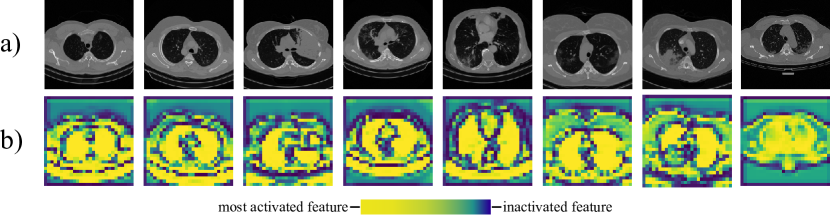

First, we provide some visualization of Activation Mapping (AM) to support that only partial feature maps are activated and crucial for the final task. As illustrated in Fig. 6, the high gradients (activation features) indicated by light pixels in AM are always in and near the lung area, demonstrating that focusing on distilling the activation features makes sense. Based on this, we propose the Hilbert Distillation to enable 2D student activation features to learn directly from 3D teacher activation features in a dimensionality-free manner.